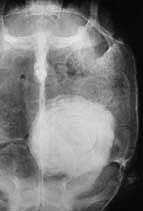

但是並非所有的結石都能經由觸診來發現,

另一個診斷方式,也是比較可靠的方式,

當然就是照X光了.雖然X光片中這顆結石很大,

不過並不罕見,有些結石甚至大到需要先擊碎

才能由腹甲的切口夾出來.